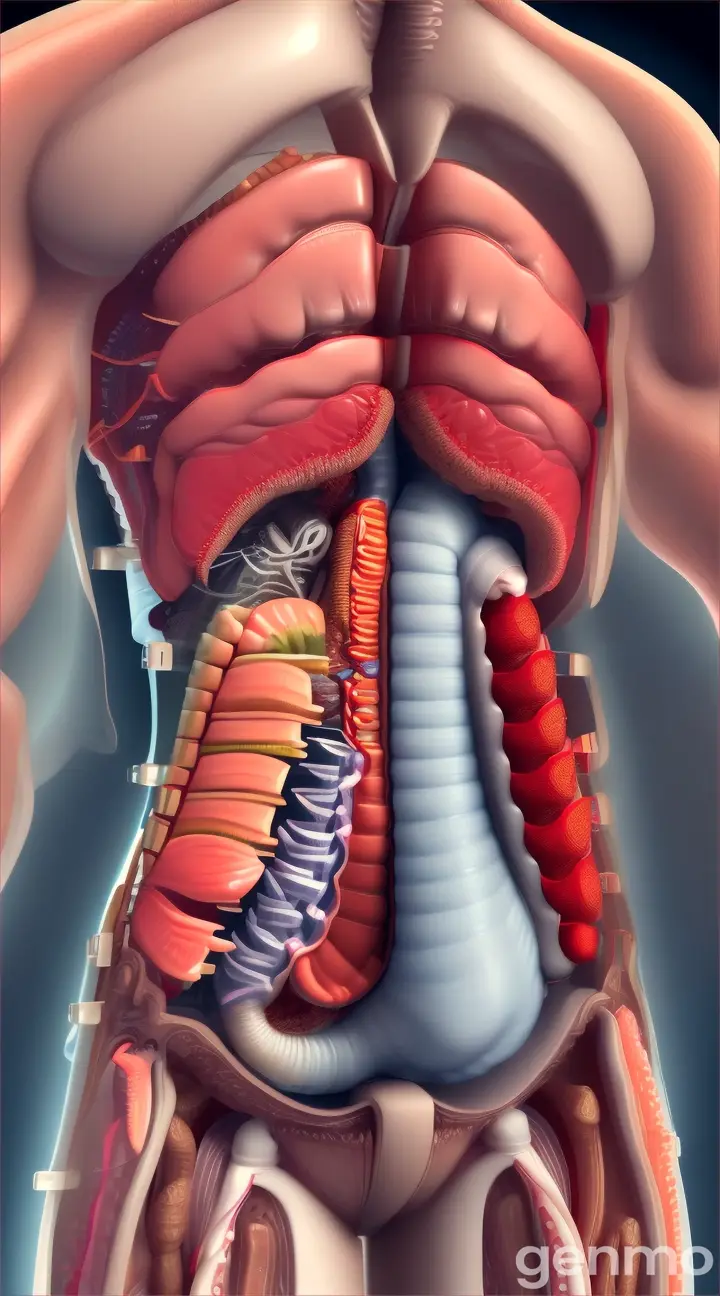

Prompt

blender